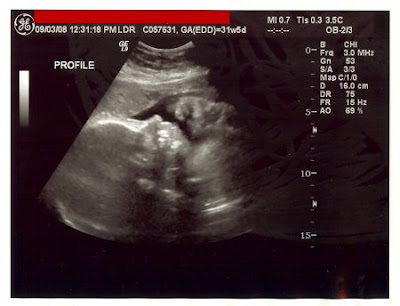

Sorry to complain. I'm down to 60 days, so ya'all only have to put up with the preggy side of me for that much longer. Think we can make it?! ;)